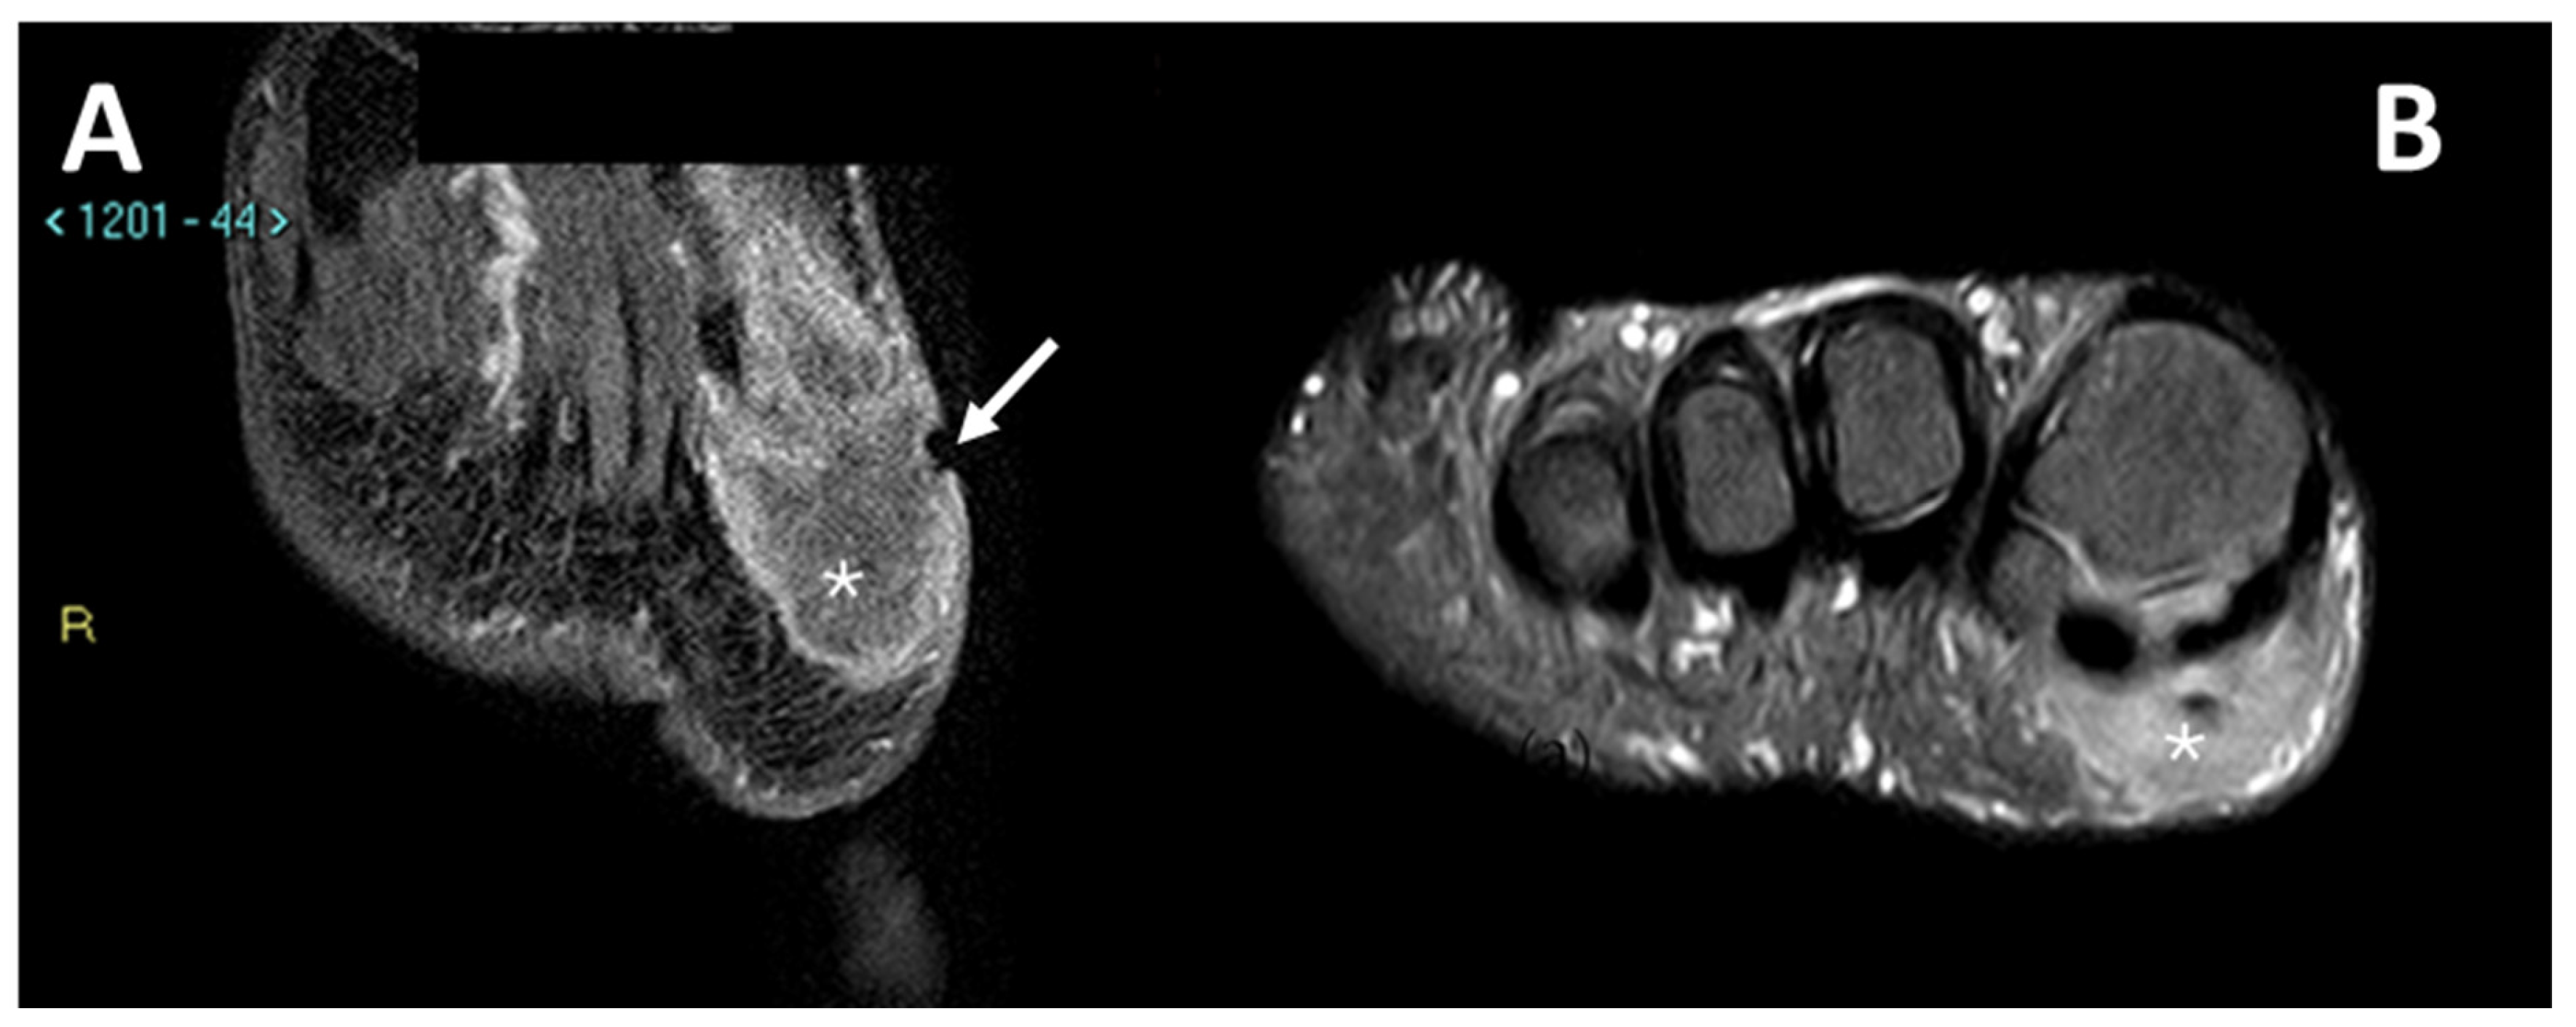

1.1. General Characteristics, History and Epidemiology

1.3. Imaging and Clinical Features

1.3.2. Magnetic Resonance Imaging

3.4. MRI Features

3.4.1. General MRI Features

3.4.2. Peritumoral Edema

3.4.3. Other MRI Features